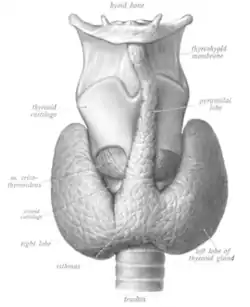

A glândula tireóide é um órgão em forma de borboleta composto por dois lobos, esquerdo e direito, conectados por uma estreita faixa de tecido, chamada de "istmo".[5] Ele pesa 25 gramas em adultos, com cada lóbulo tendo cerca de 5 cm de comprimento, 3 cm de largura e 2 cm de espessura, e o istmo cerca de 1,25 cm de altura e largura.[5] A glândula é geralmente maior nas mulheres do que nos homens e aumenta de tamanho durante a gravidez.[5][6]

A tireoide está perto da parte frontal do pescoço, apoiada e em torno da parte frontal da laringe e traquéia.[5] A cartilagem tireóide e a cartilagem cricóide ficam logo acima da glândula, abaixo do pomo de Adão. O istmo se estende do segundo ao terceiro anéis da traquéia, com a parte superior dos lobos estendendo-se até a cartilagem tireóide e a parte inferior em torno do quarto ao sexto anéis traqueais.[7] Os músculos infra-hióideos situam-se à frente da glândula e o músculo esternocleidomastóideo ao lado.[8] Atrás das asas externas da tireoide estão as duas artérias carótidas. A traquéia, a laringe, a faringe inferior e o esôfago ficam atrás da tireoide.[6] Nessa região, o nervo laríngeo recorrente[9] e a artéria tireoide inferior passam próximos ou no ligamento.[10] Normalmente, quatro glândulas paratireoides, duas de cada lado, situam-se em cada lado entre as duas camadas da cápsula da tireoide, na parte posterior dos lobos da tireoide.[5]

Às vezes, há um terceiro lóbulo presente, chamado lóbulo piramidal.[6] Quando presente, esse lobo freqüentemente estica o osso hióide a partir do istmo tireoidiano e pode ser de um a vários lobos divididos.[5] A presença desse lóbulo varia em estudos relatados de 18,3%[12] a 44,6%.[13] Mostrou-se que surge com mais frequência do lado esquerdo e ocasionalmente se separa.[12] O lobo piramidal também é conhecido como pirâmide de Lalouette.[14] O lobo piramidal é um remanescente do ducto tireoglosso, que geralmente se deteriora durante a descida da glândula tireoide.[6] De fato, pequenas glândulas tireoides acessórias podem ocorrer em qualquer lugar ao longo do ducto tireoglosso, desde o forame ceco da língua até a posição da tireoide no adulto.[5] Um pequeno chifre na parte posterior dos lobos da tireoide, geralmente próximo ao nervo laríngeo recorrente e à artéria tireoidiana inferior, é chamado de tubérculo de Zuckerkandl.[10]

Outras variantes incluem um músculo elevador da glândula tireoide, conectando o istmo ao corpo do osso hióide[6] e a presença da pequena artéria ima da tireoide.[6]